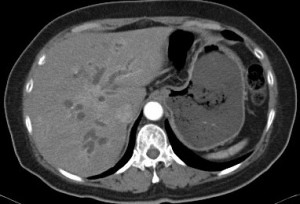

膽管癌

膽管結構包括肝外及肝內膽管 , 而膽管癌可以影響膽管中的任何位置。

膽管癌可基於其發生位置而作出分類︰

• 肝內膽管癌

• 肝外膽管癌

• 肝門膽管癌 (發生在肝外膽管與肝臟相接處)

• Klatskin Tumour (發生在左右兩肝管匯流形成總肝管處)